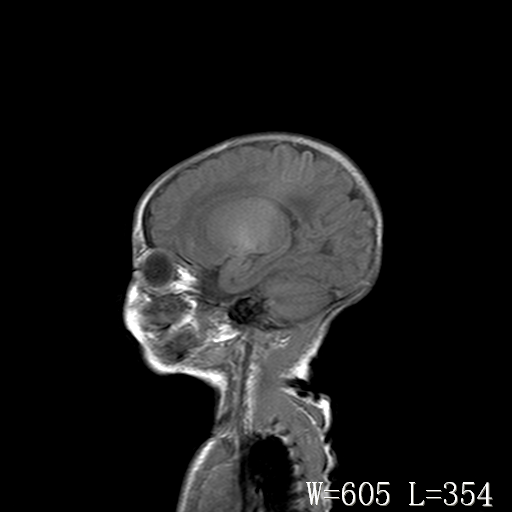

标题: PED3338:脑部病变?

男,4天,发复抽搐1天。

新生儿正常颅脑

脑干形态欠规则,信号增高,不知怎么解释?

脑干背侧面t1高信号是,新生儿正常已经髓鞘化好的部位